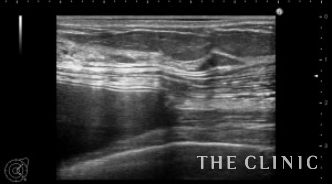

エコーでバッグの入っている部位(乳腺下か、大胸筋下か)や、カプセル拘縮の状態やバッグの破損を診断します。

この方はバッグは大胸筋下、軽度のカプセル拘縮を認めました。

バッグが挿入されている部位は、本人は覚えていないこともあり、術前のエコー診断は安全にバッグを取り出すために不可欠です。